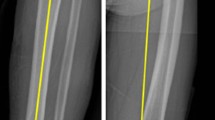

Correlation between leg alignment and medial–lateral gap size difference (Fig. 1)

The correlation between the coronal leg alignment and the medial–lateral gap difference in extension showed a high correlation of r2 = 0.62. This is documented in a constant increase of difference in extension: HKA 2° = 1.0 mm difference, HKA 5° = 2.6 mm, HKA 10° = 5.2 mm and HKA 15° = 7.8 mm.

At all flexion angles, this correlation was low r2 = 0.05 at 30°, to 0.11 at 60° to 0.16 at 90°.